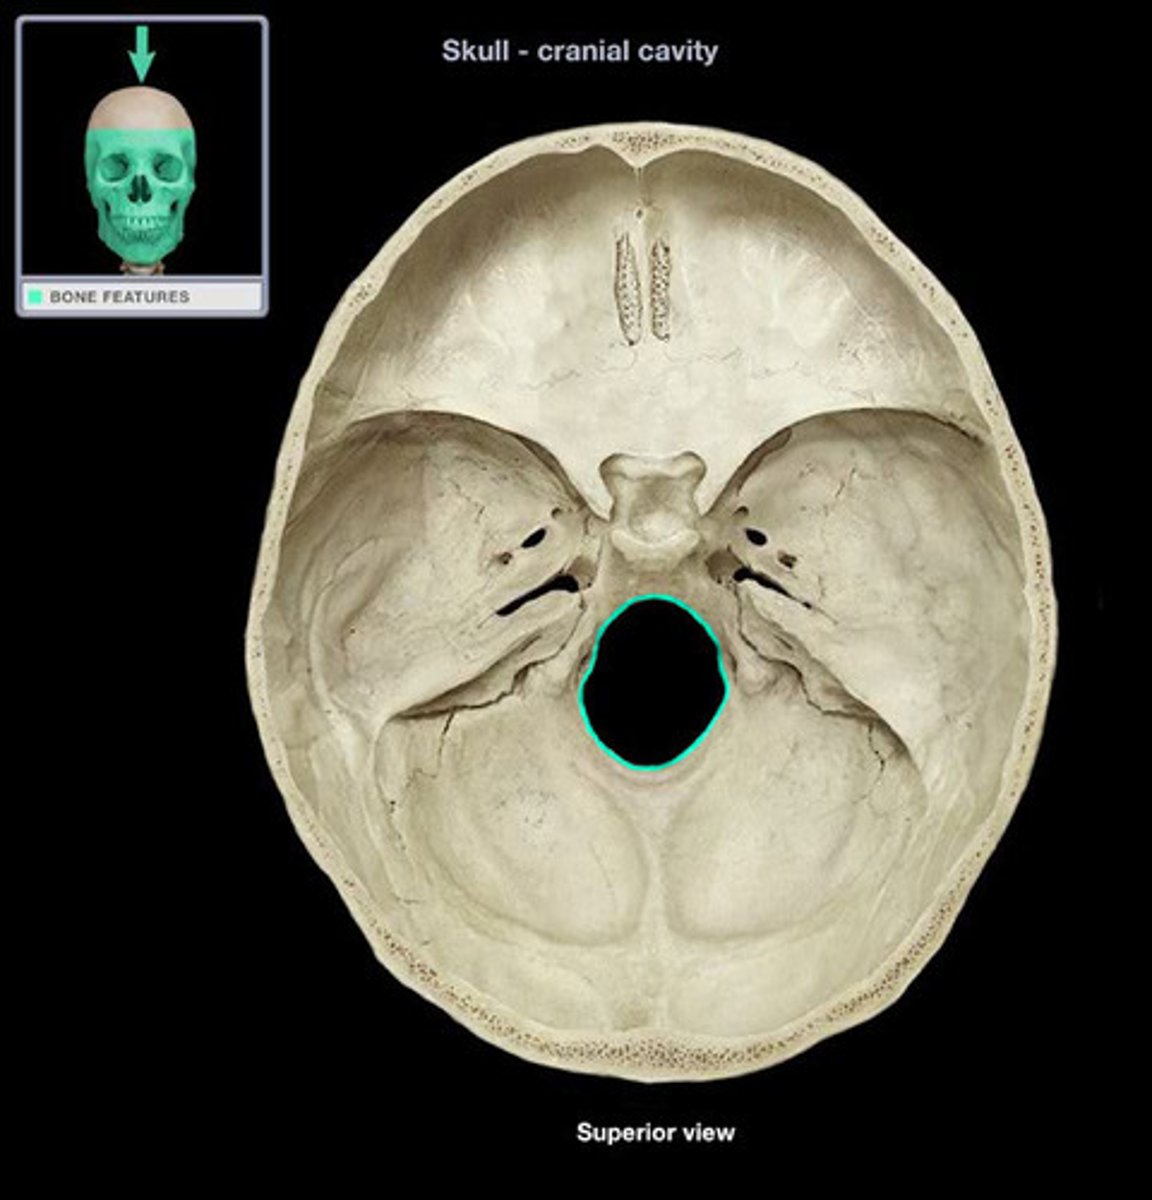

foramen magnum

large opening at the based of the skull that transmits the spinal cord, vertebral arteries, and spinal accessory nerve (CN XI)

cervicomedullary junction

transition between the medulla oblongata and upper cervical spinal cord (C1-C2) that is located at the level of the foramen magnum

*houses ascending/descending tracts (decussation) and nuclei that influence breathing, CV control, and CN 9-12